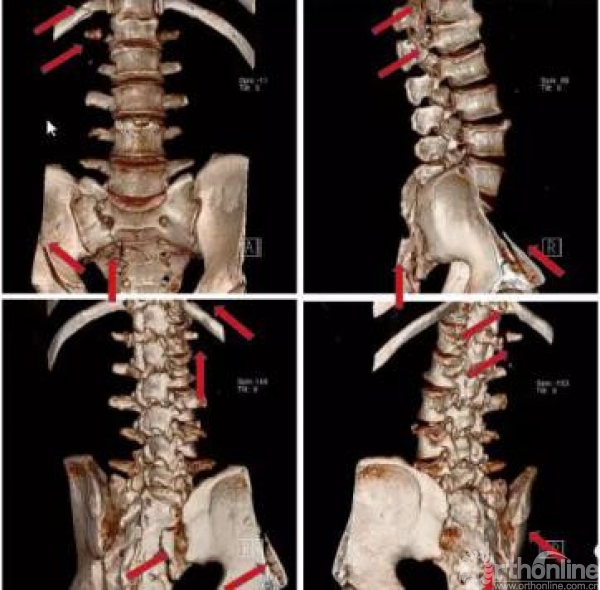

术前骨盆CT三维重建(2017.09.17)

术前骶尾椎CT三维重建(2017.09.17)